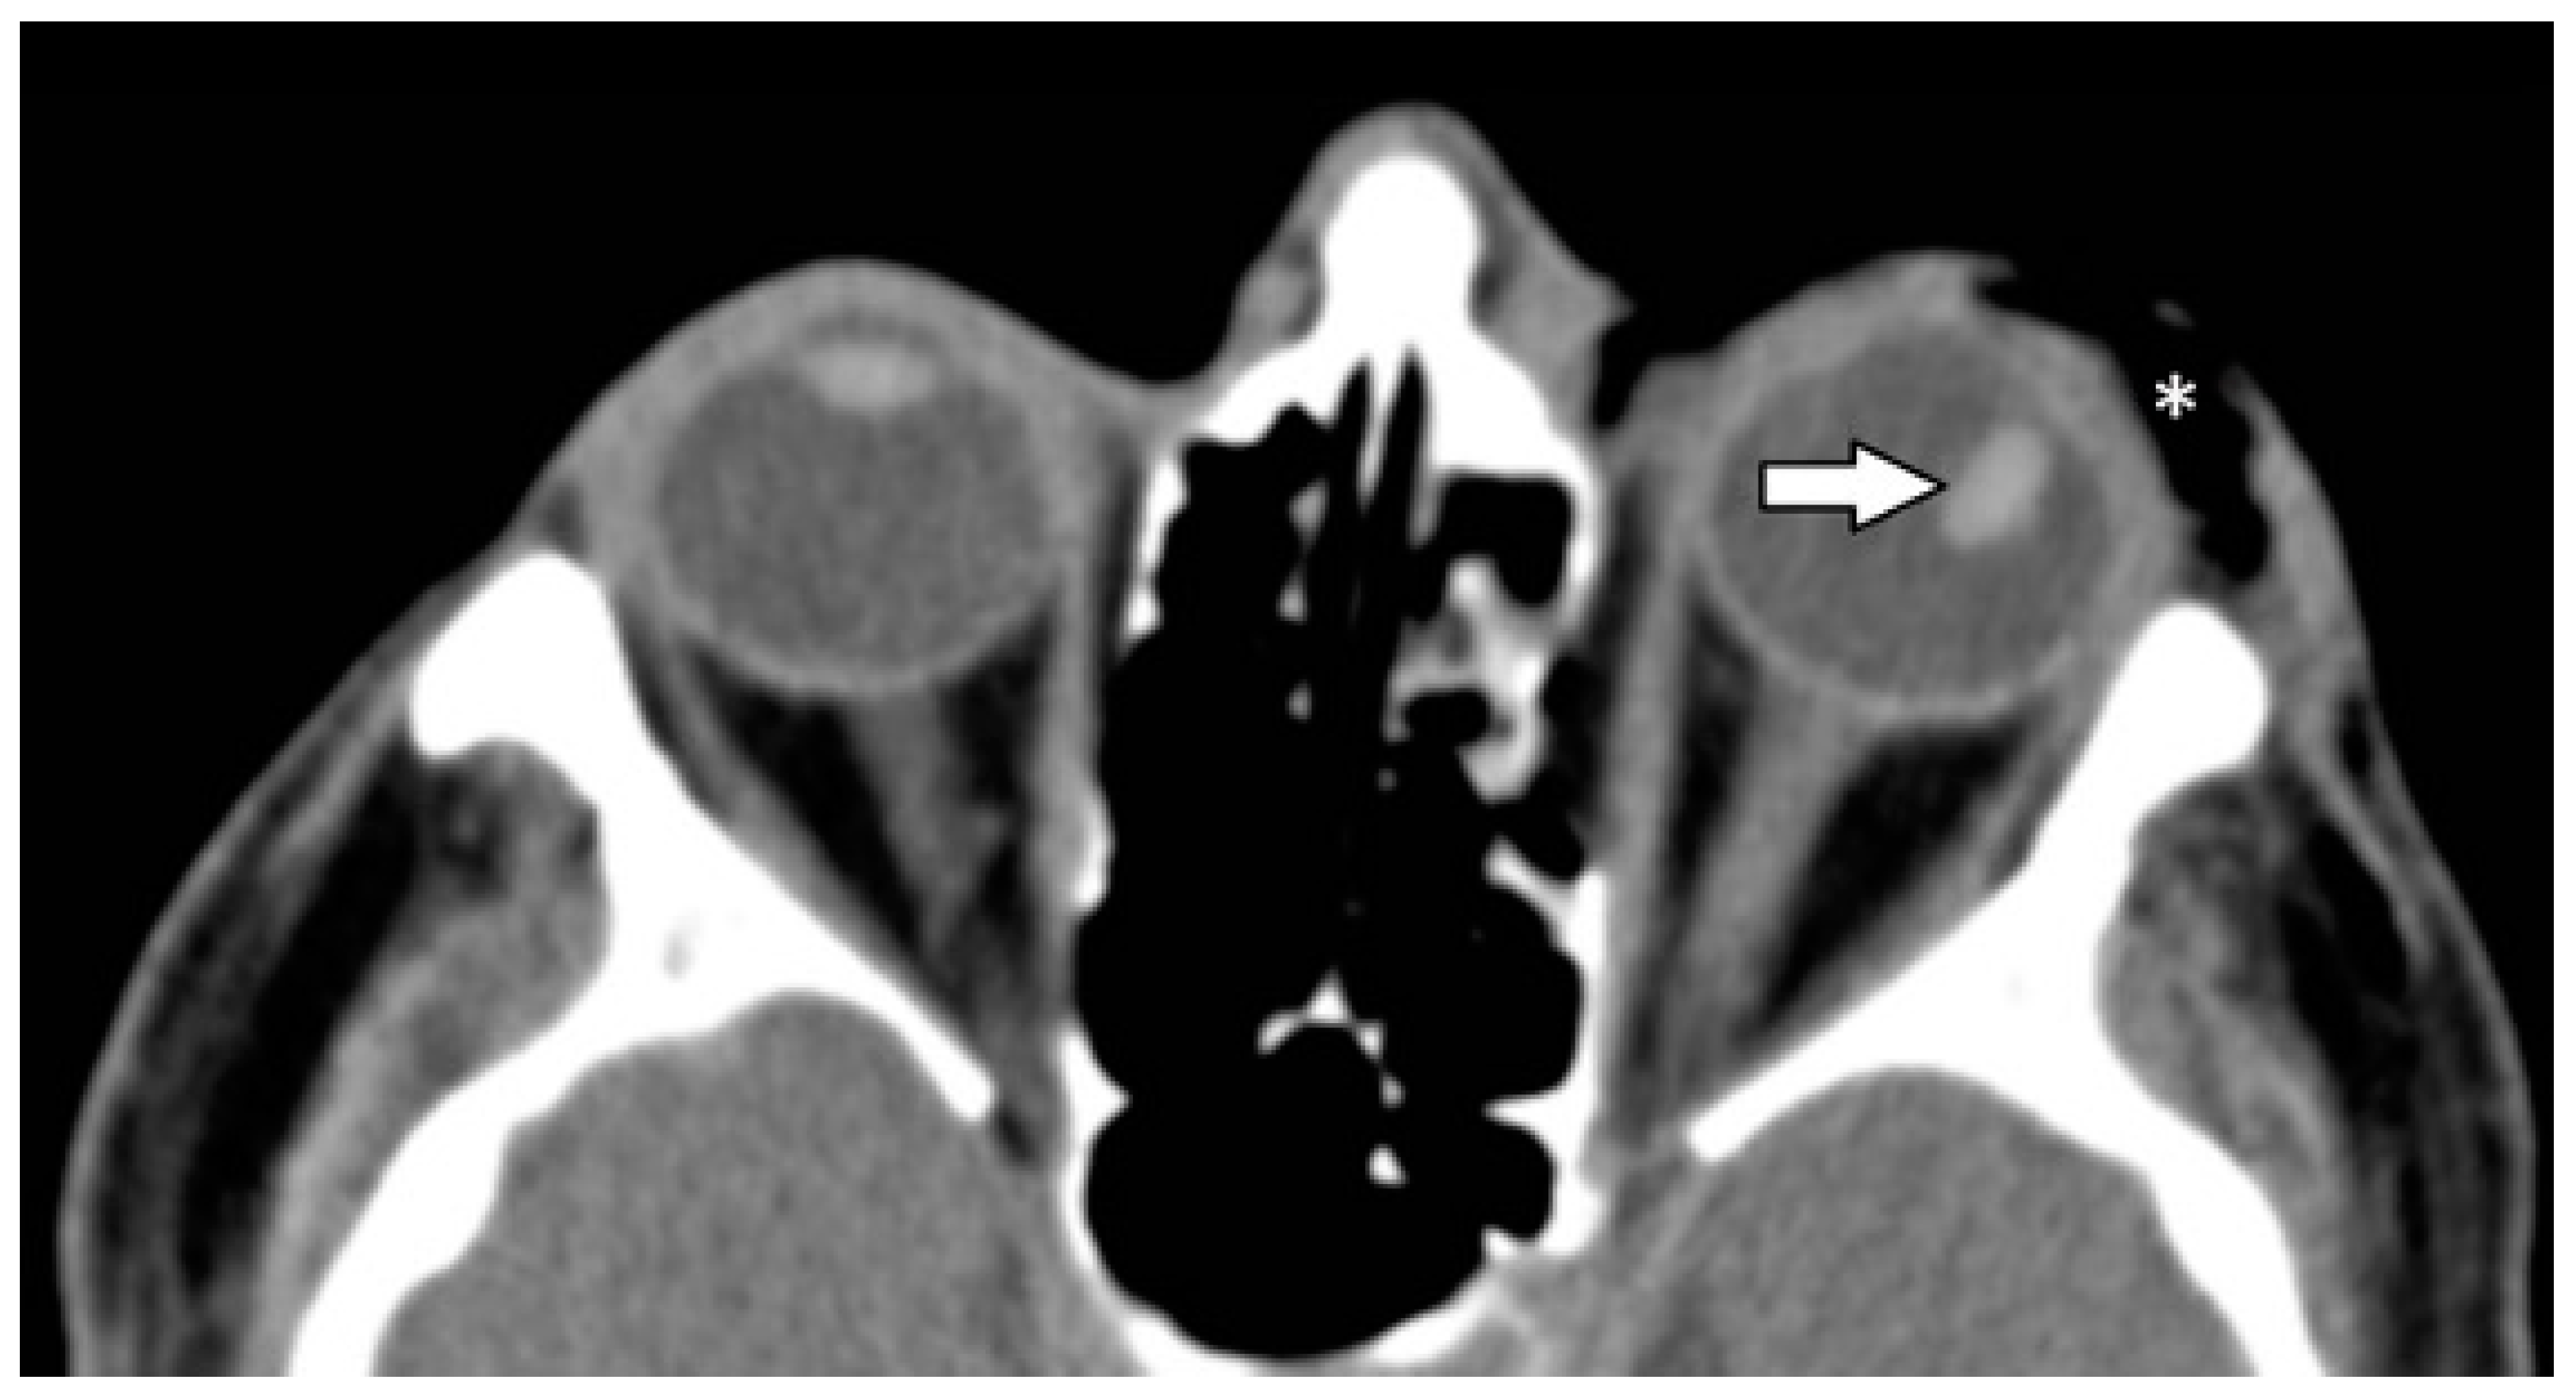

| Ocular globe and lens | 38 (37.6) | |

| Deformed globe or vitreous body | 24 (23.8) | |

| rupture of ocular globe | 7 (6.9) | |

| dislocated lens | 6 (5.9) | |

| intraconal foreign body | 1 (1.0) | |